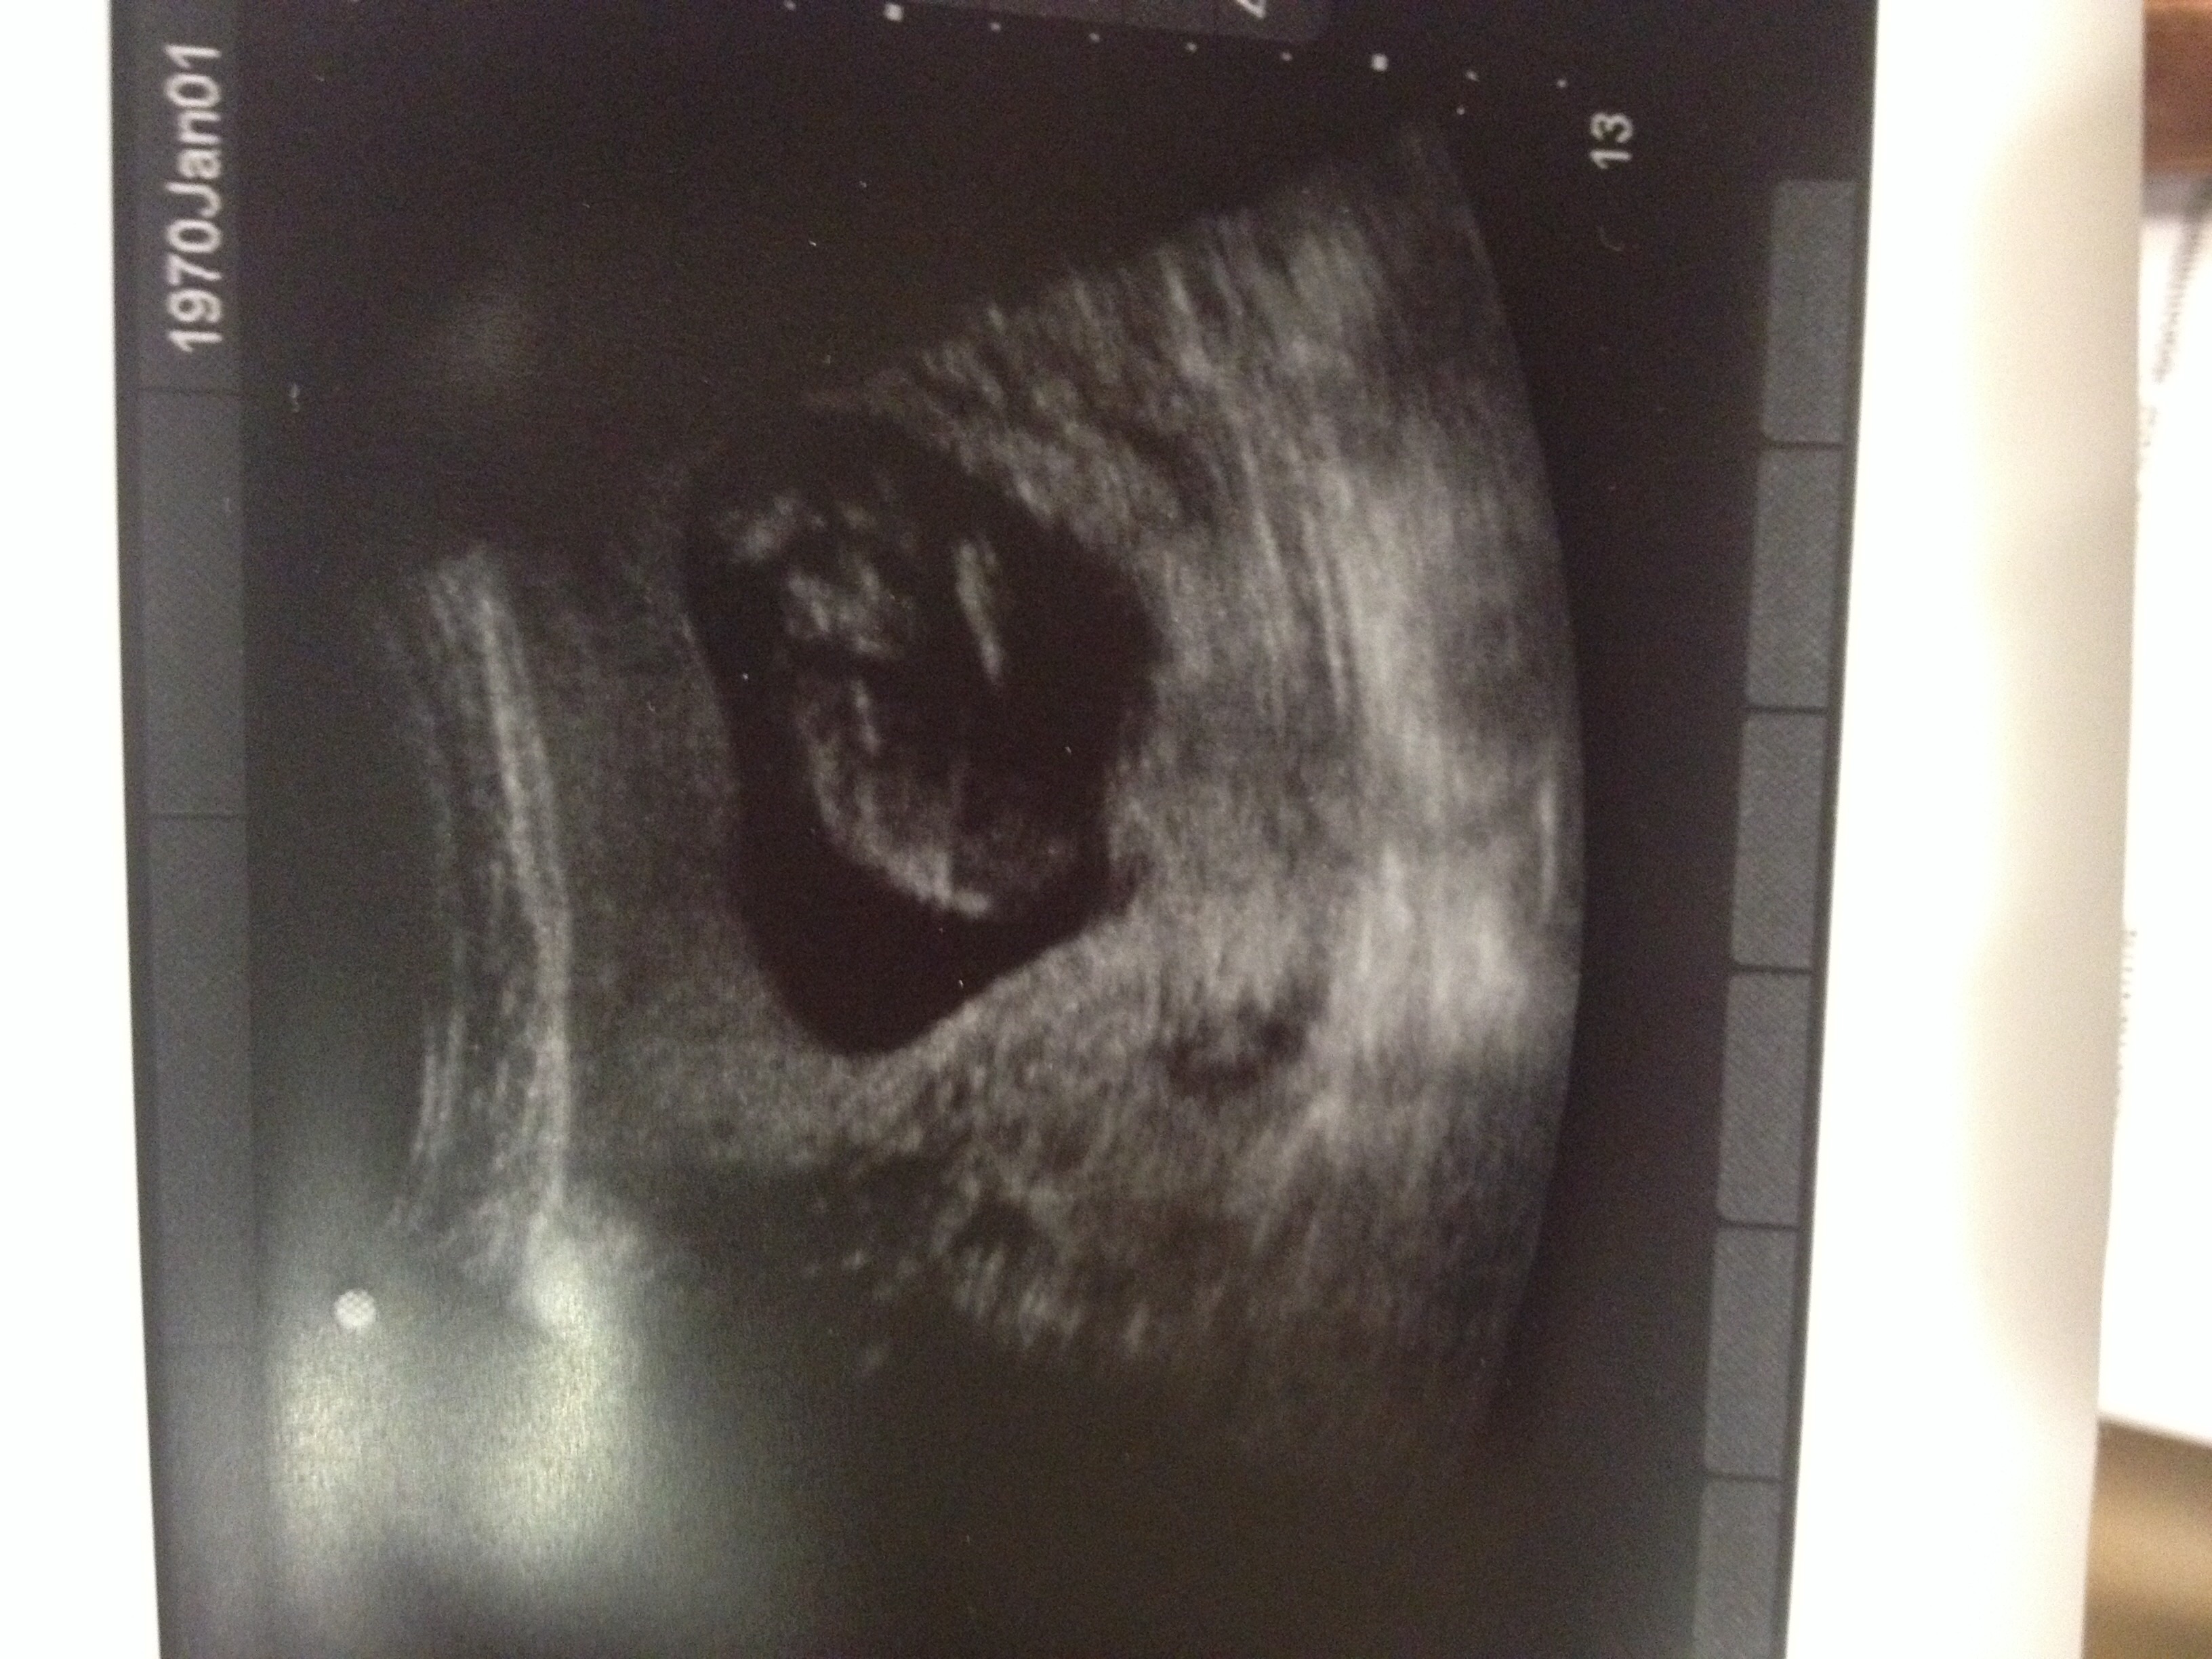

Re: RAMZI me please - just for fun